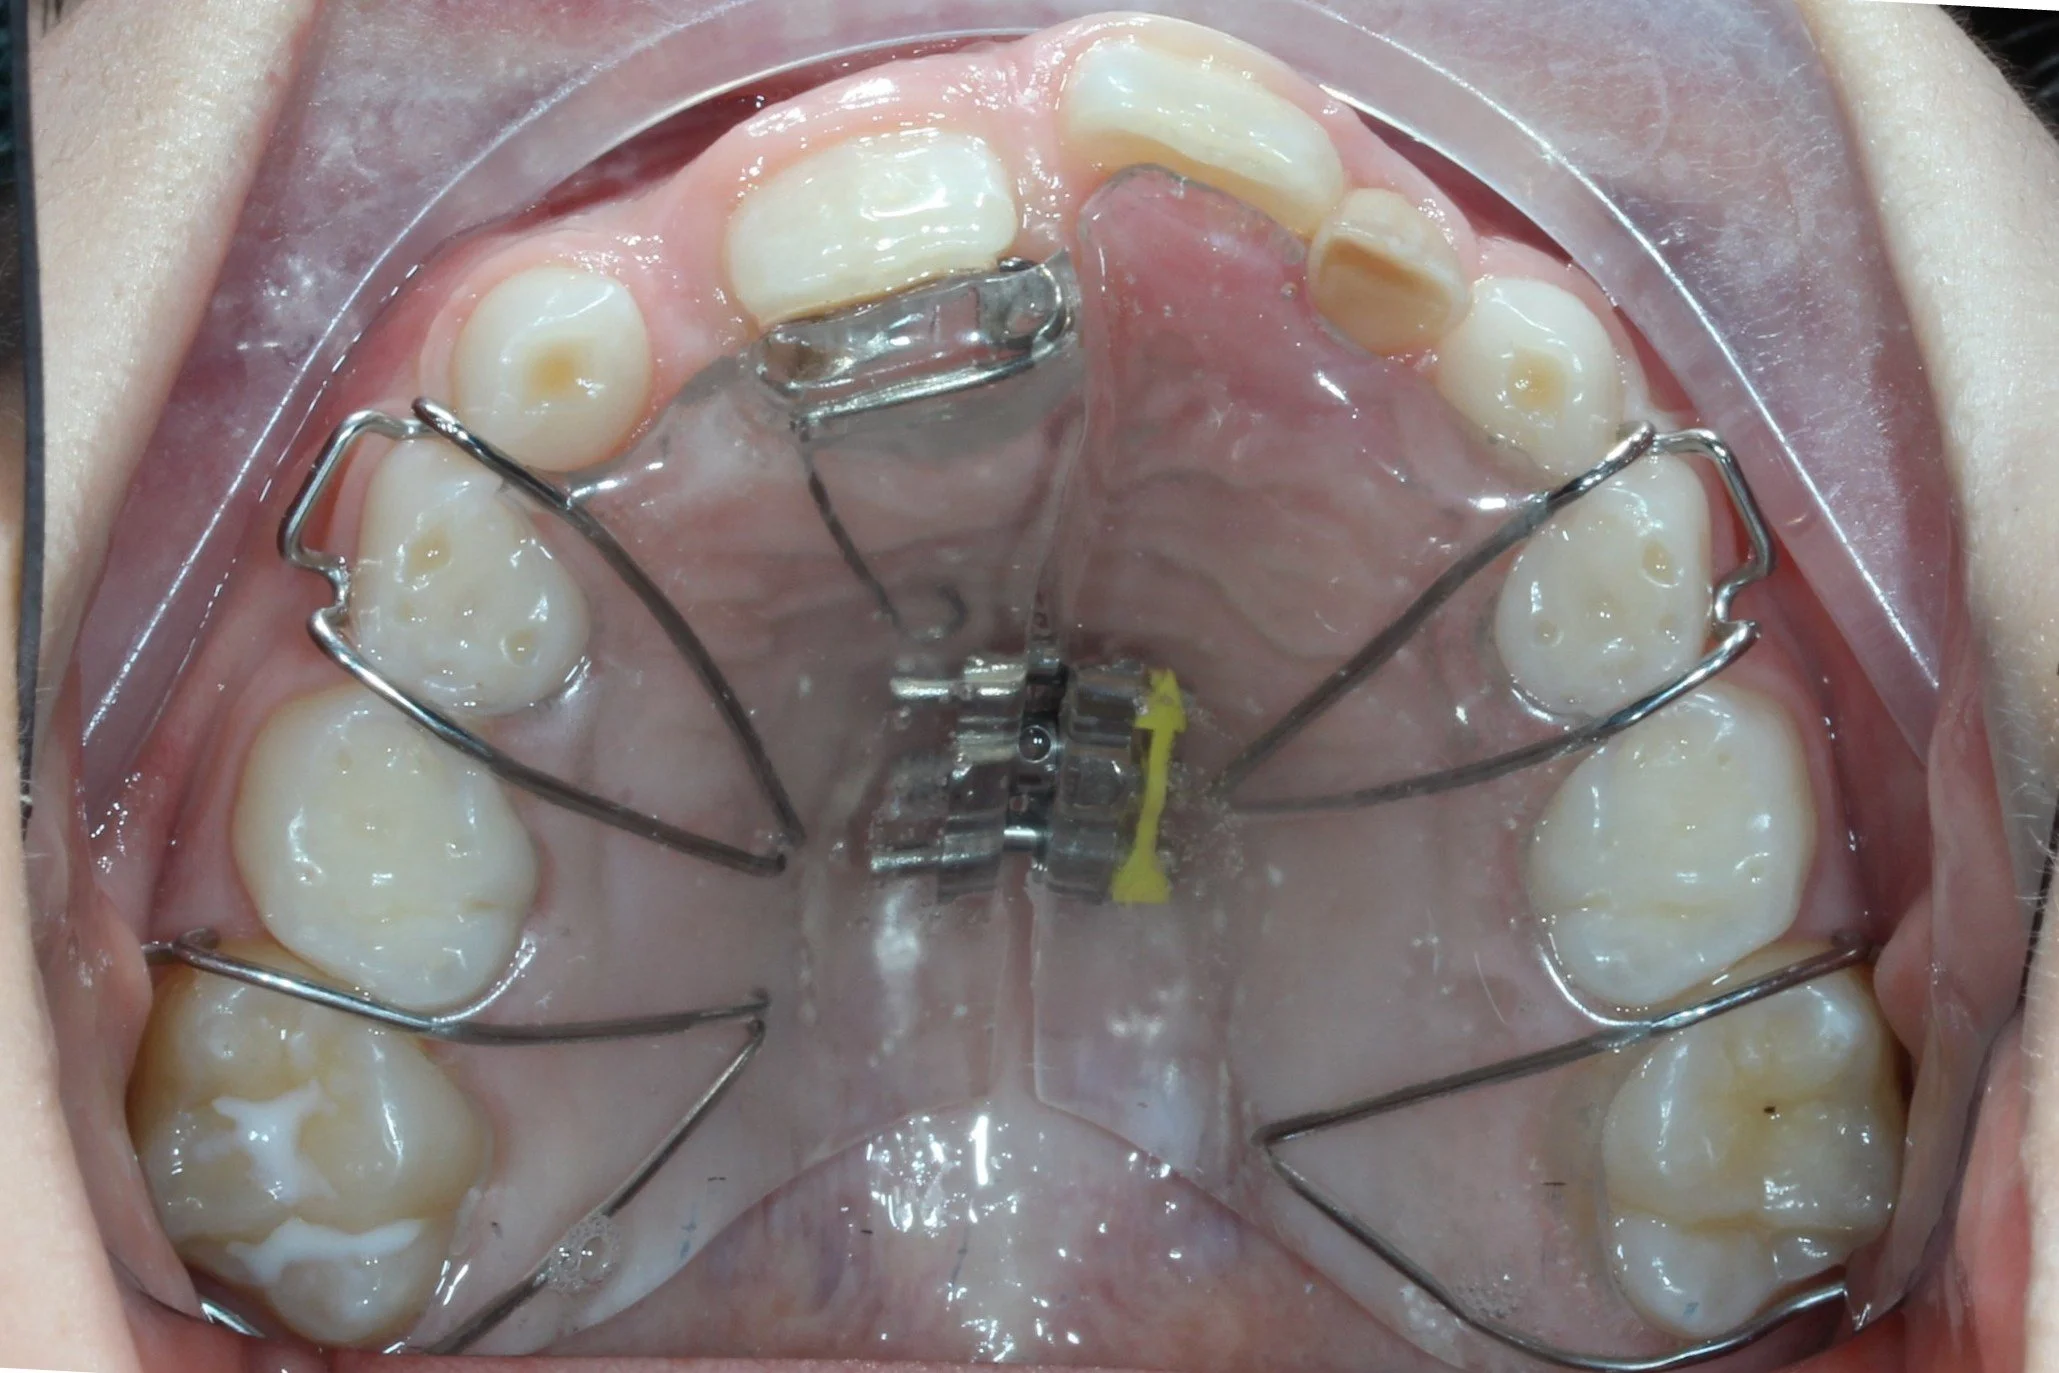

alt="RME expander brace"

Rapid Maxillary Expansion (RME) brace bonded to the upper premolar and molar teeth. Used in a growing adolescent to orthopaedically expand the upper jaw bone

RME brace in place before expansion

RME brace in place after expansion